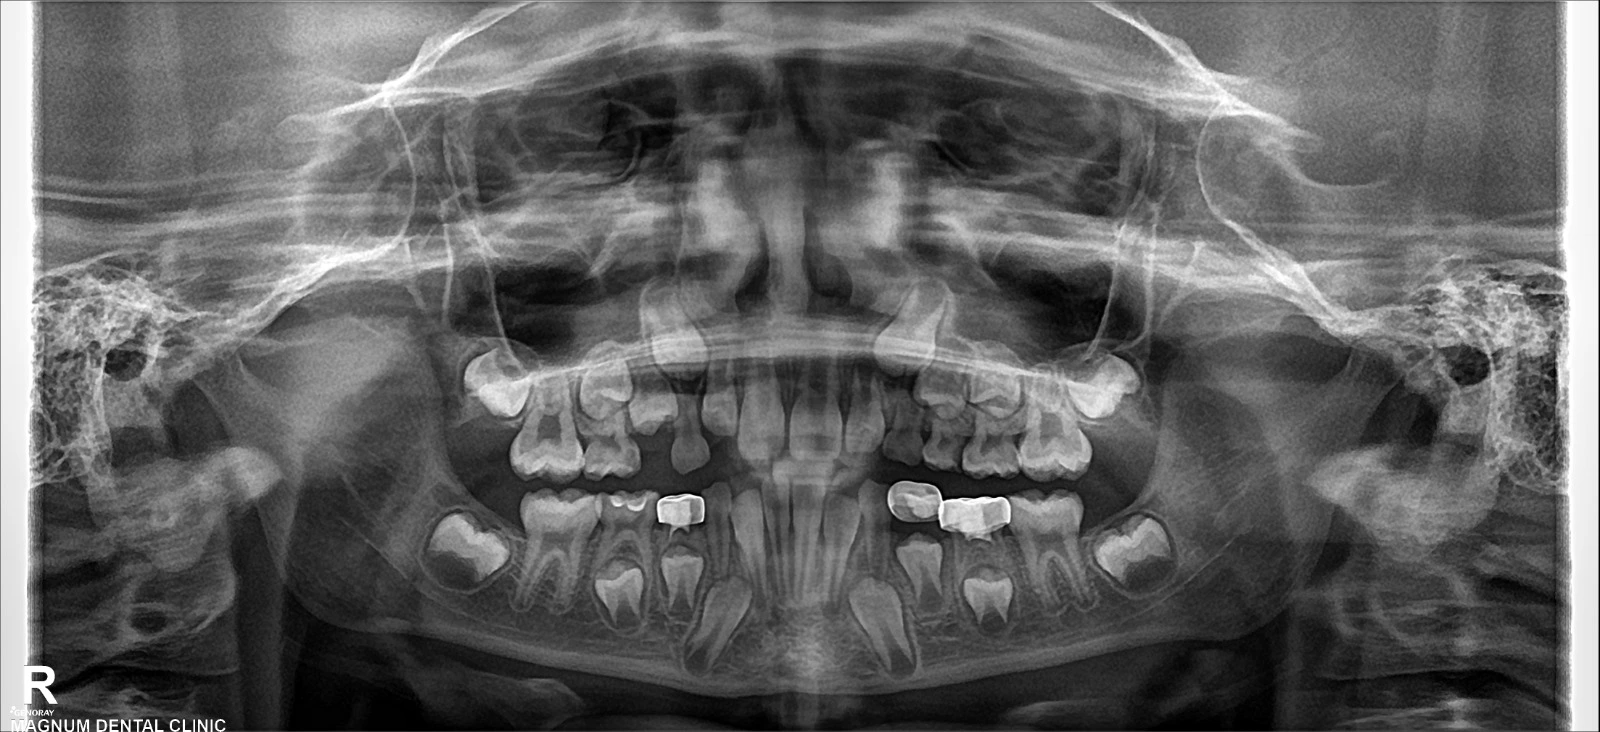

A complete oral examination and an orthopantomogram (OPG) were performed. The extraction socket healed, and the adjacent tooth (#K) received vital pulp therapy and a stainless steel crown. It was necessary to preserve the area of the permanent first premolar (#21).

Without intervention, the loss of space may cause crowding or impaction. The procedure involved applying a unilateral band and loop space maintainer to tooth #K.

This immobile appliance would stabilize the space until the permanent tooth erupts and achieves the proper alignment.